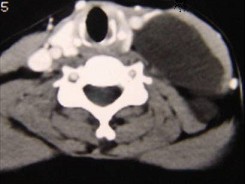

20.50岁女性患者,体检发现右侧甲状腺有较硬结节,CT扫描如图所示,请选择正确的描述和答案  (    )

正确答案:ABE